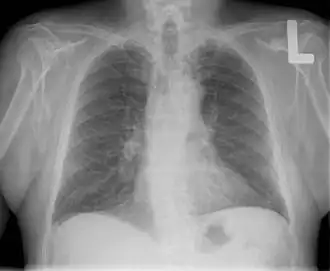

Röntgenfoto

De patiënt kijkt ons aan. We zien onder andere hart, longen,

middenrif, luchtpijp, onder het middenrif

een luchtbel in de maag, bovenarmbeenderen, sleutelbeenderen, ribben.